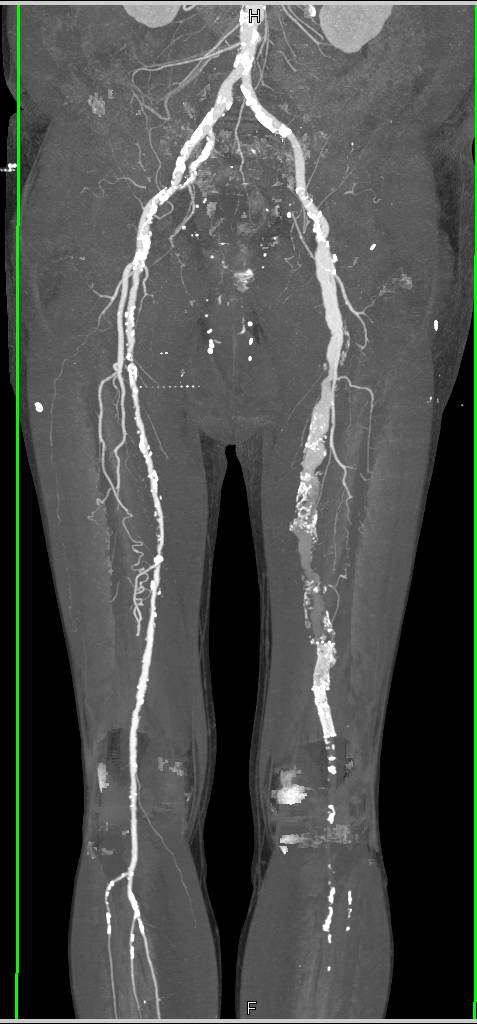

Superior Mesenteric Artery (SMA) and Celiac Occlusion with Graft off Aorta to Supply the Vessels Distally